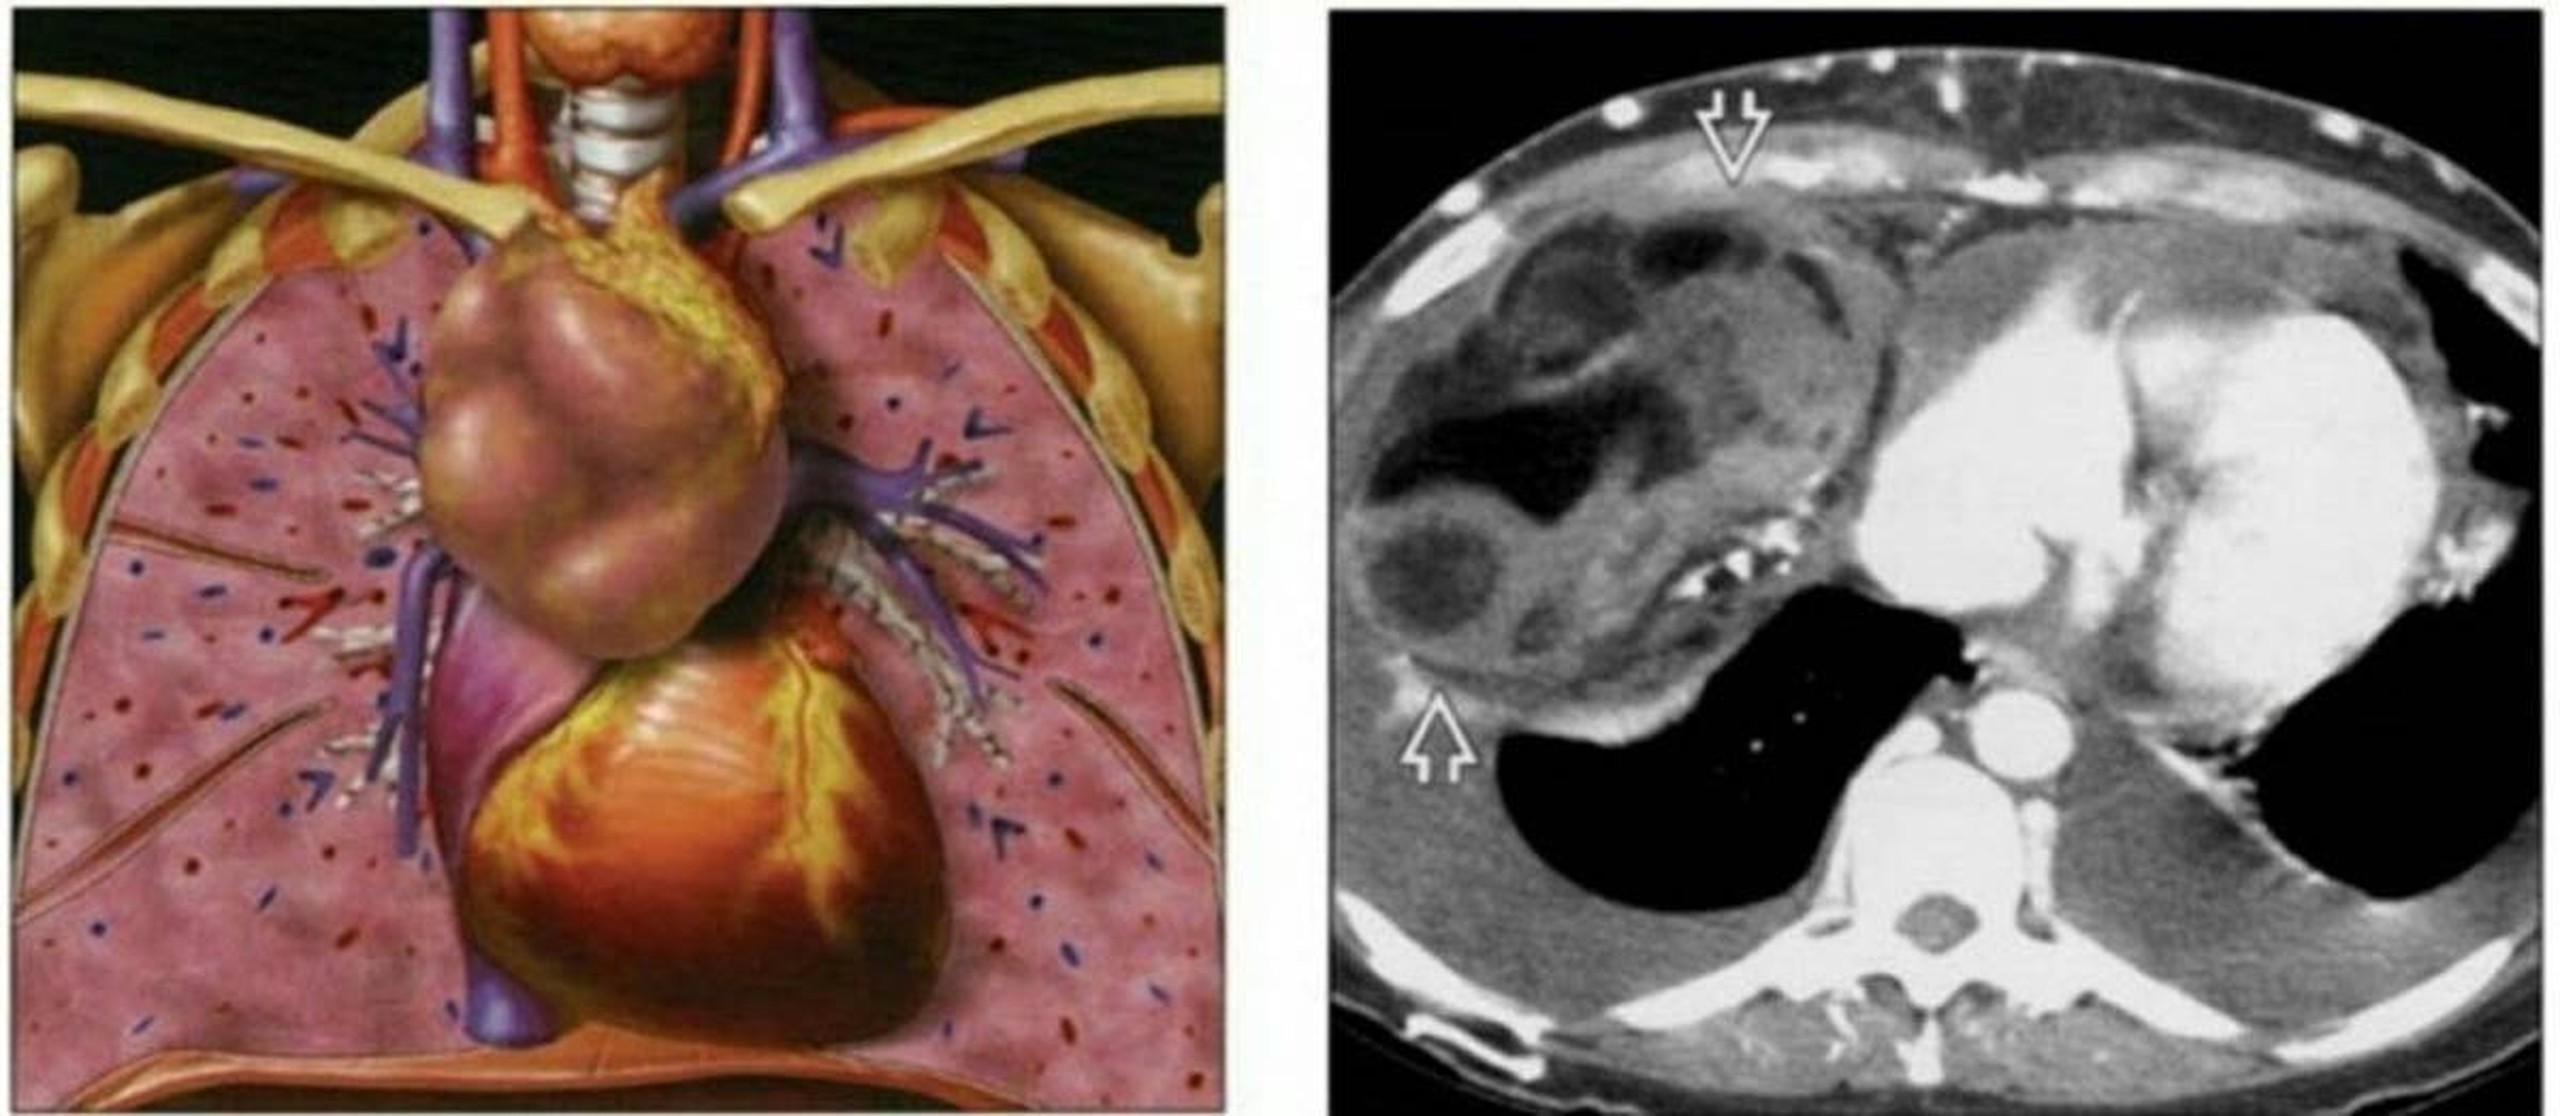

U trung thất là khối u nằm ở trong lồng ngực, khối u có thể là lành tính hoặc ác tính, thường phát triển âm thầm và ít khi được phát hiện sớm. Ở người lớn các khối u có thể không có triệu chứng hoặc gây ra triệu chứng tắc nghẽn đường thở xảy ra nhiều ở trẻ em.

Trung thất là một vùng ở giữa ngực không bao gồm phổi, được bao quanh bởi xương ức ở phía trước, cột sống ở phía sau và phổi ở mỗi bên. Trung thất của bạn chứa tim, động mạch chủ, thực quản, tuyến ức, tuyến giáp, khí quản, hạch bạch huyết và dây thần kinh. Tuyến ức của bạn là một cơ quan thuộc hệ thống miễn dịch của bạn. Hệ thống bạch huyết của bạn, hay hệ thống bạch huyết, cũng là một phần của hệ thống miễn dịch và giúp bảo vệ cơ thể bạn.

U trung thất rất hiếm, chỉ xảy ra ở dưới 1% dân số. Hầu hết hình thành ở phần trước (phía trước) của trung thất. Các loại phổ biến nhất là u tuyến ức, u nang trung thất lành tính và u lympho.